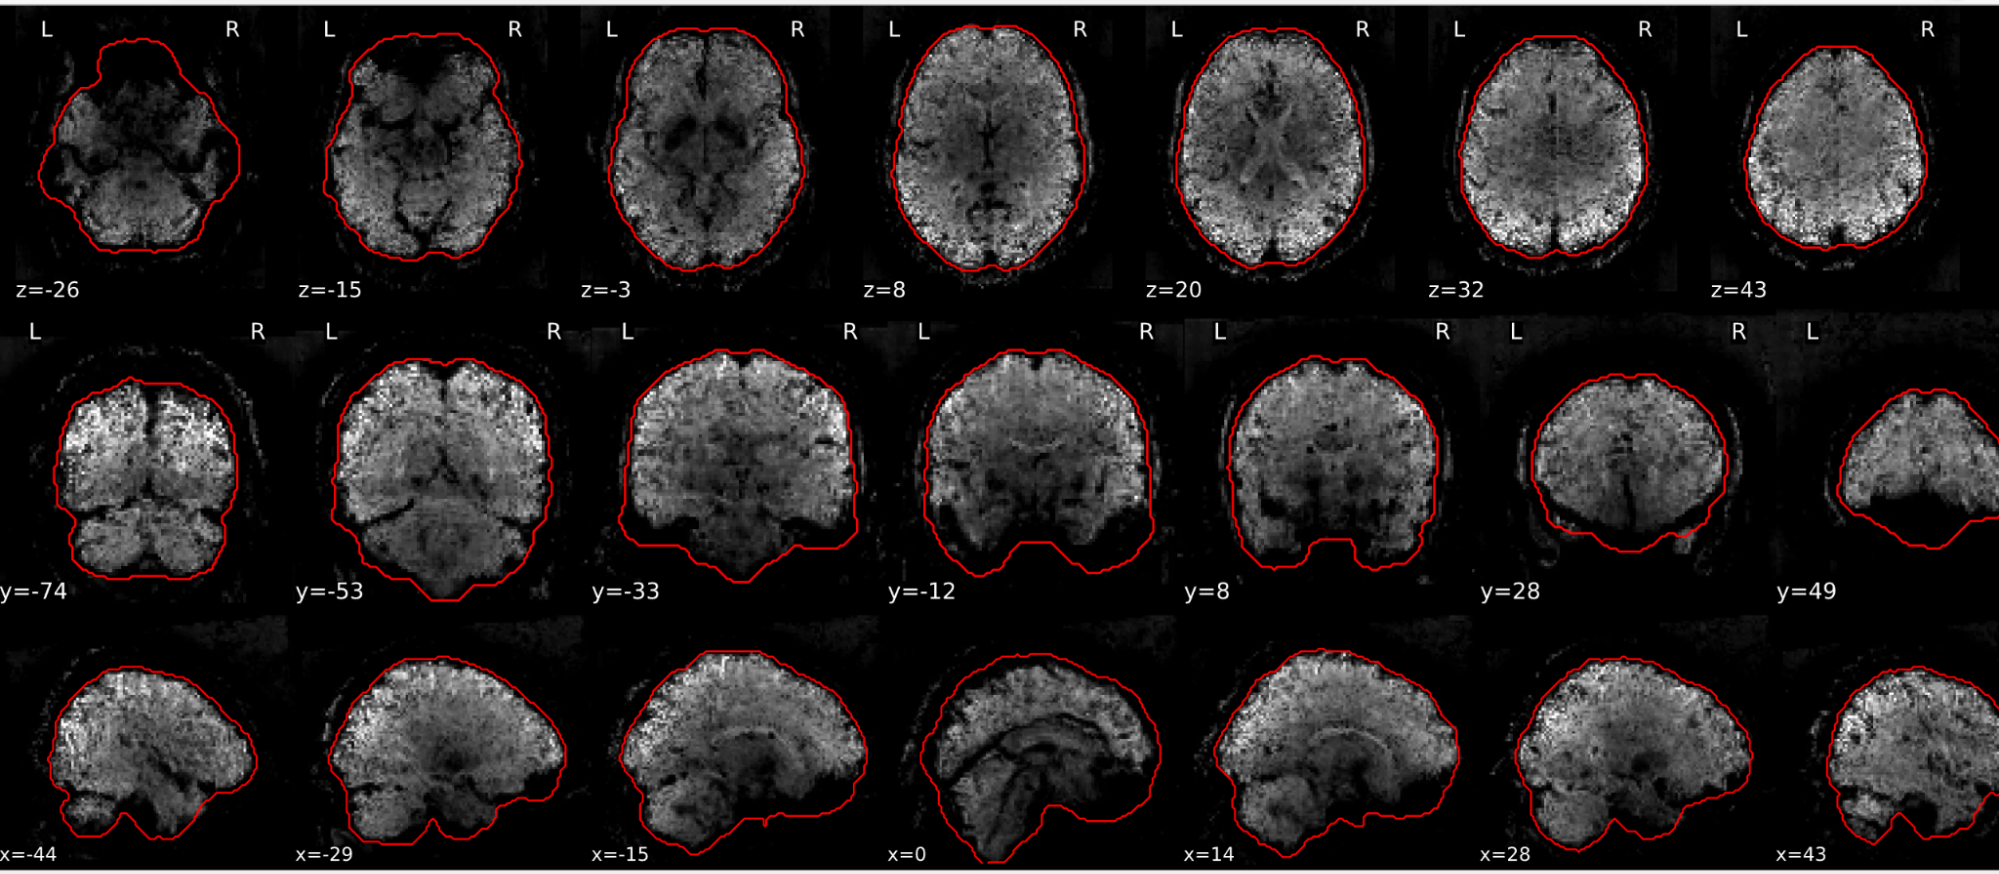

EPI tSNR

In the signal to noise ratio images of the resting state image the desired signal is compared to the amount of background noise. It is important to check all the views (sagittal, coronal, axial) because some artefacts (e.g., stripes) may be evident only in one particular view.

Example of a good subject

- Signal to noise is symmetrically distributed and there is no signal distortion

Example of a bad subject

- Asymmetry

- Potential signal distortion (might represent an artefact)

- Signal drop-out

- Stripes artefact

Clear large artefact (e.g., zebra stripes in example 1) are worth the exclusion of the subject. If you are unsure, check the other quality metrics for that subject to decide whether they should be excluded.

Summary

| good | bad |

|---|---|

| Symmetrical distribution of noise and signal | Asymmetry |

| No disruptions of the signal (no “black patches”) |

Potential signal disruptions (could be related to artefacts) |

| No stripes (sign of high motion) |

Signal drop |

| Stripe artefacts (“zebra” stripes due to motion) |